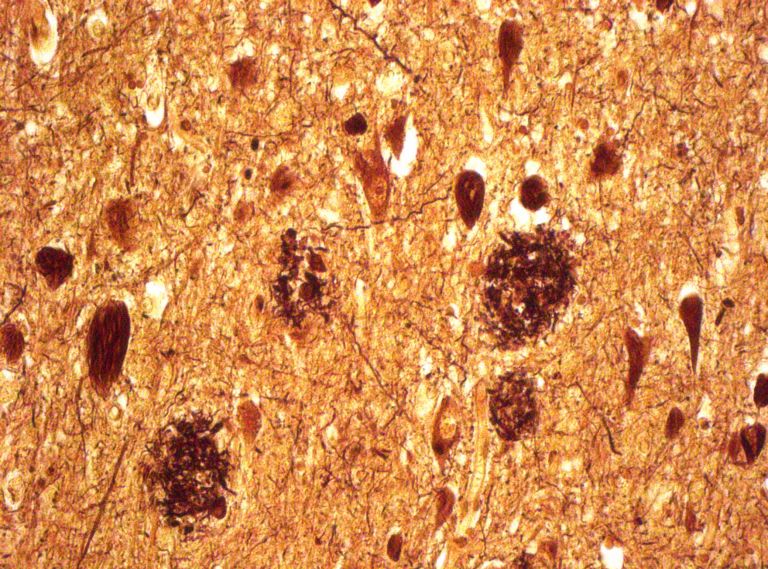

Der deutsche Neuropathologe Max Bielschowsky entwickelte eine Färbemethode, die mittels Versilberung speziell die senilen Plaques bei Alzheimer-Patienten sichtbar macht. Post mortem, natürlich. Ein schönes Bild mit makabrem Hintergrund. Mehr über die biochemischen Veränderungen im Gehirn erfahren Sie in den Artikeln Altern – (nicht nur) eine Frage der Biologie und Das Gehirn in seinen reifen Jahren.

Bild von Dr. Jakob Matschke, Leiter AG forensische Neuropathologie, Universitätsklinikum Hamburg-Eppendorf

Senile Plaques lagern sich in der grauen Hirnsubstanz ab, wenn ein Eiweiß – das so genannte Amyloid-Vorläuferprotein – nicht korrekt abgebaut wird. Entzündungen sowie Erkrankungen des Fett– oder des Zuckerstoffwechsels können die Plaquebildung begünstigen. Im Schnitt erreichen die Ablagerungen einen Durchmesser von 50 Mikrometern. Das Auftreten von Plaques ist eine von mehreren anatomischen Veränderungen im Gehirn, anhand derer Pathologen nach dem Tod eine Alzheimer-Erkrankung diagnostizieren können.